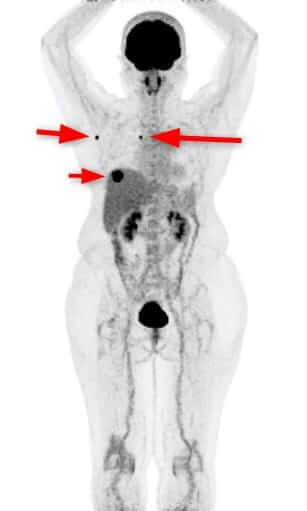

悪性リンパ腫 多発性リンパ節転移 左肺下葉腫瘍

原因不明がん/多発性リンパ節転移/左肺下葉腫瘍画像